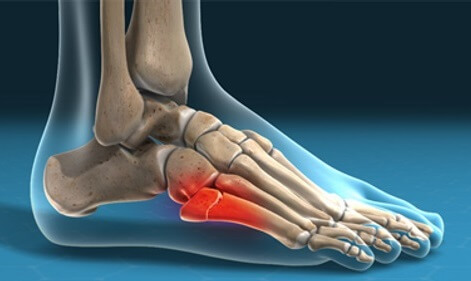

Inflammation in the sinus tarsi canal, a small tunnel between the heel bone and ankle bone

Causes: Ankle sprain, scar tissue, subtalar instability, flat feet

Symptoms: Deep pain, instability, stiffness, pain with ankle movements

Full Article: Sinus Tarsi Syndrome